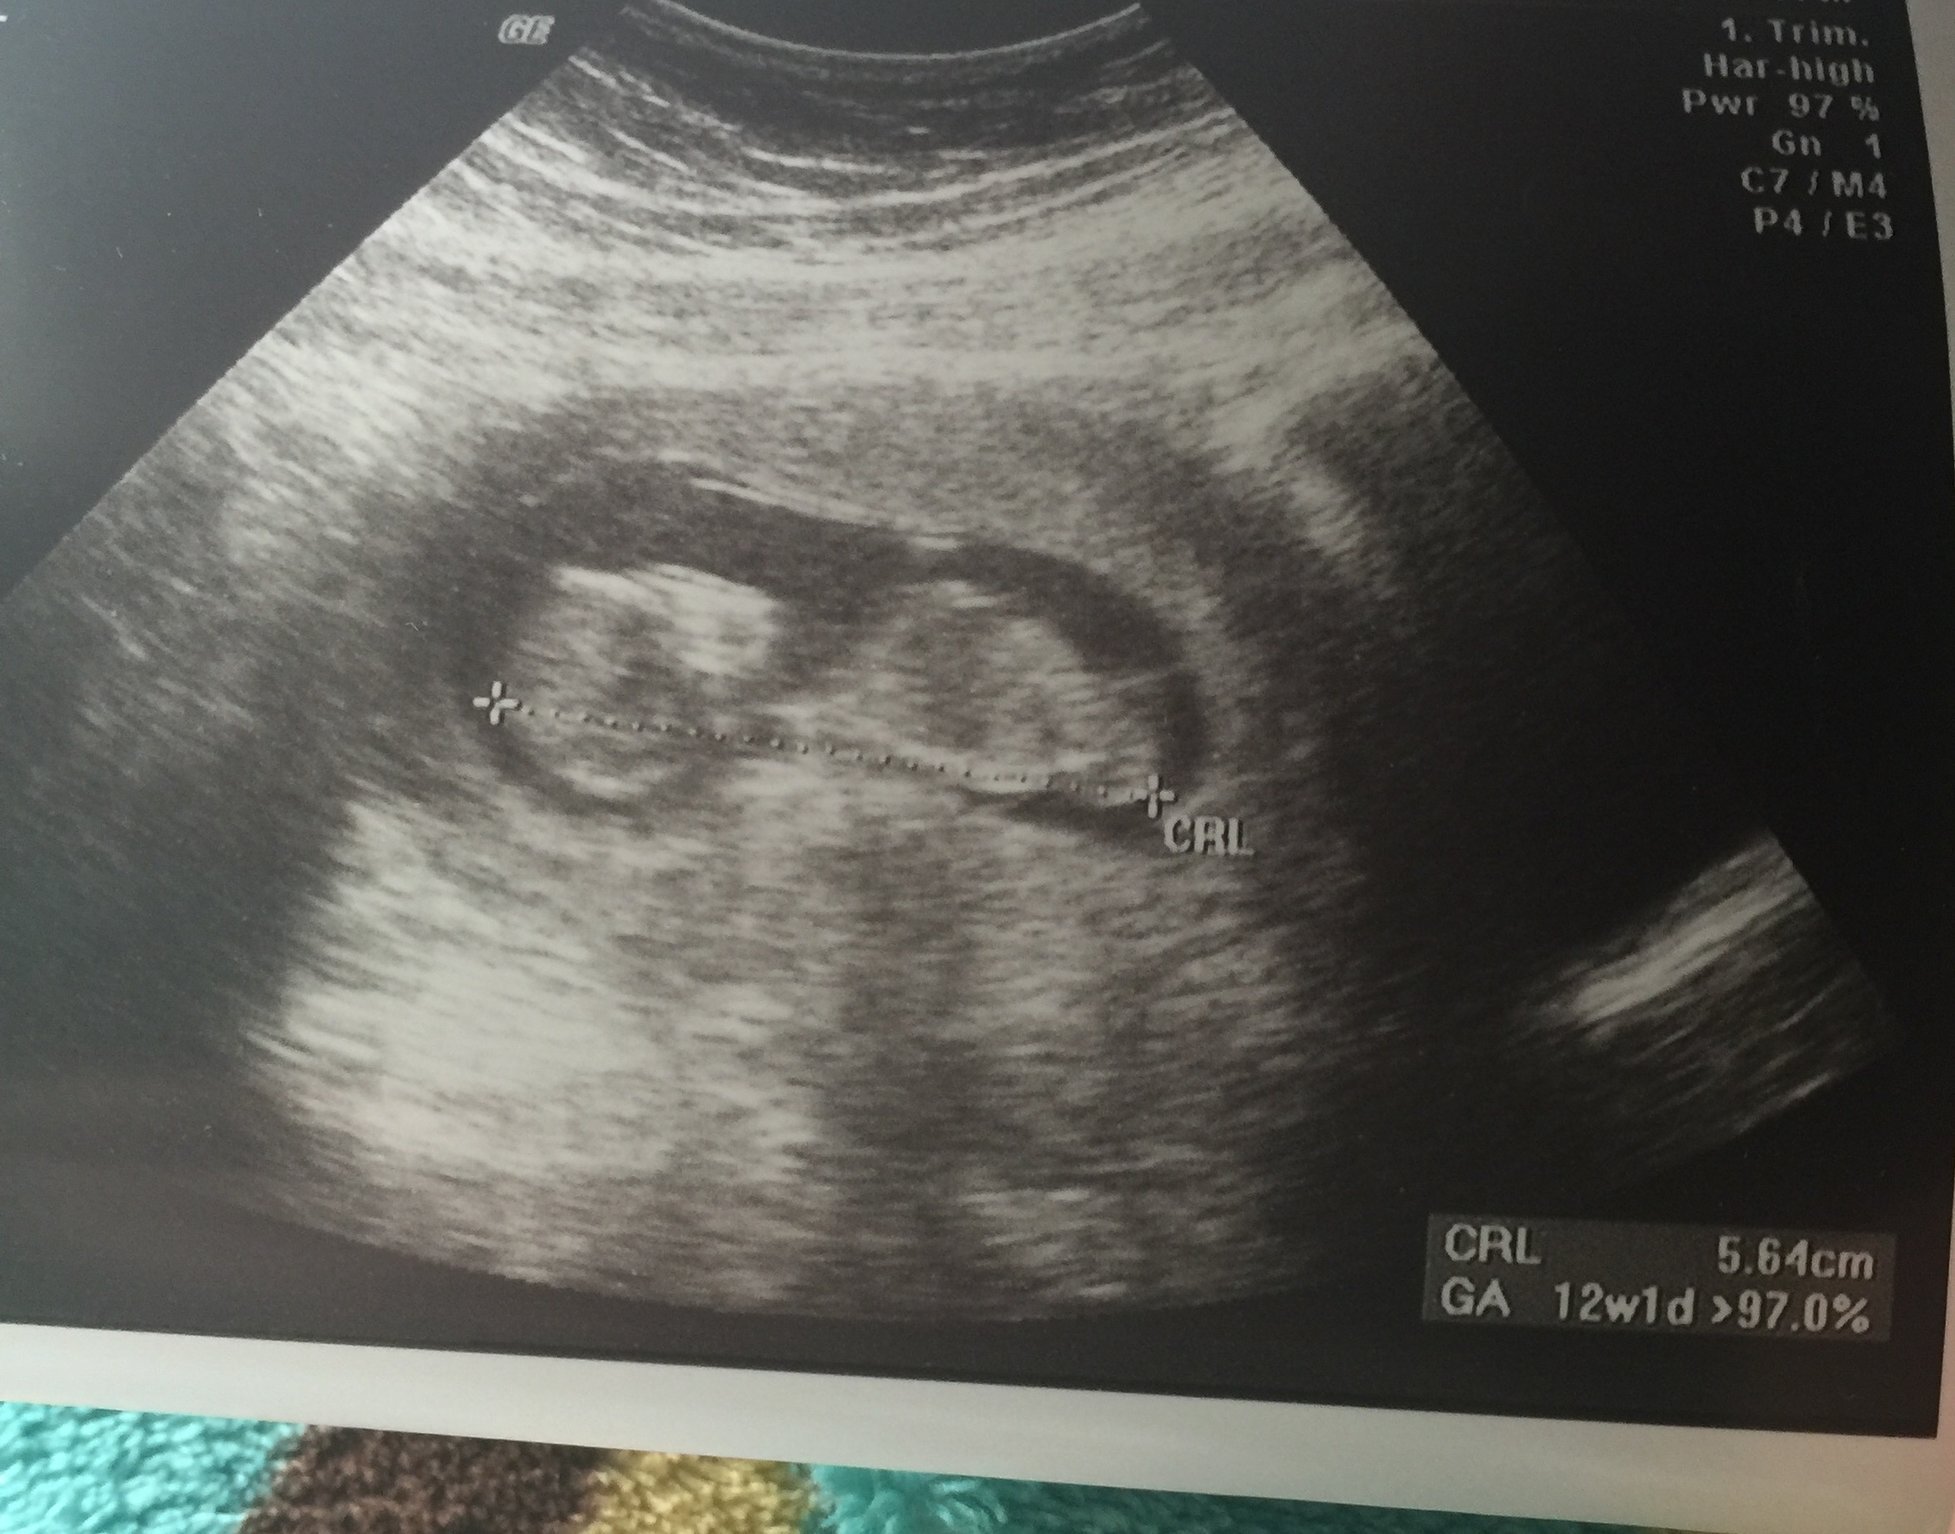

So I had my 1st appointment and ultrasound this afternoon. Wasn't sure of my LMP and I had my IUD taken out April 11th. So I was assuming I got preggo instantly and was about 8/9 weeks along.

My doctor thought I was probably 6 weeks so we went and did a dating US.... I got pregnant while my IUD was still in and had no idea. My doctor said wow that's a giant baby lol 12 weeks due December 13 so sad to say I'm moving over to dec 16 bmb! Loved hanging with you ladies! Good luck everyone!!